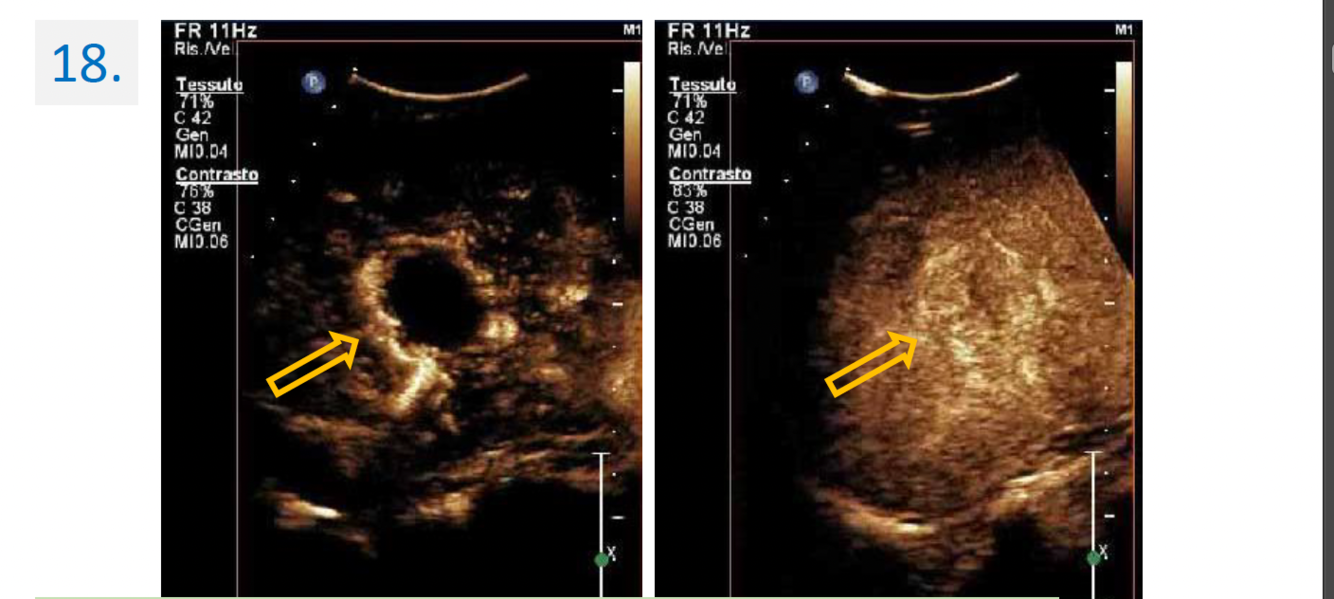

6.